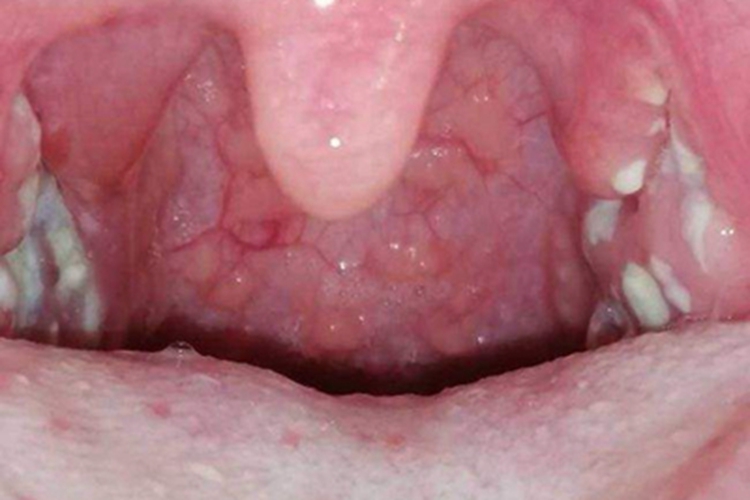

急性化脓性扁桃体炎的症状可以表现为扁桃体出现大小不一的白斑,可伴有高热、疼痛等不适。本病多与链球菌有关,需遵医嘱治疗。

急性化脓性扁桃体炎可导致扁桃体黏膜出现白斑,大小不一,患者自觉剧烈咽痛,并有吞咽痛。可伴有畏寒、高热、头痛等不适症状。